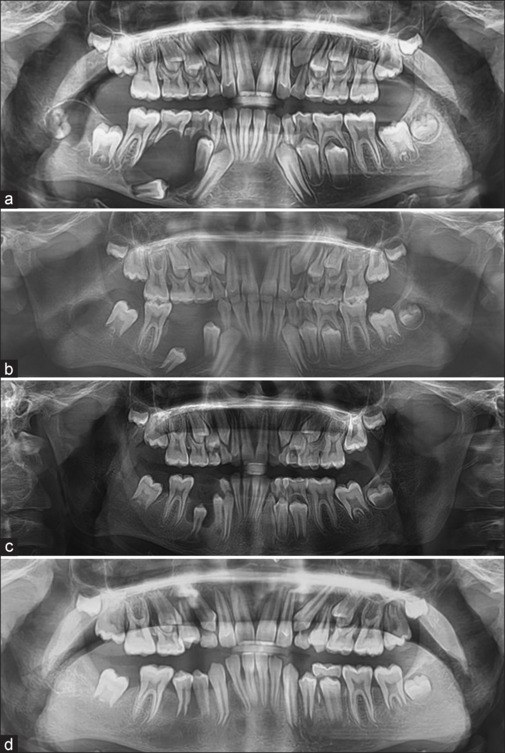

Special care is required for the management of jaw lesions in pediatric population. The following article describes the decompression technique as the least aggressive approach for the management of pediatric mandibular odontogenic keratocyst. A custom-made acrylic splint was fabricated around teeth, and it was attached to a piece of Foley's catheter to be used as a decompression port. Subsequent radiographs revealed a decrease in the size of radiolucency, bone formation, and eruption of permanent premolars during a time period of 1 year only. This technique prevents damage to permanent tooth buds, vital anatomic structures like inferior alveolar neurovascular bundle, and fracture of bone which may occur with other common techniques of management of odontogenic keratocyst.